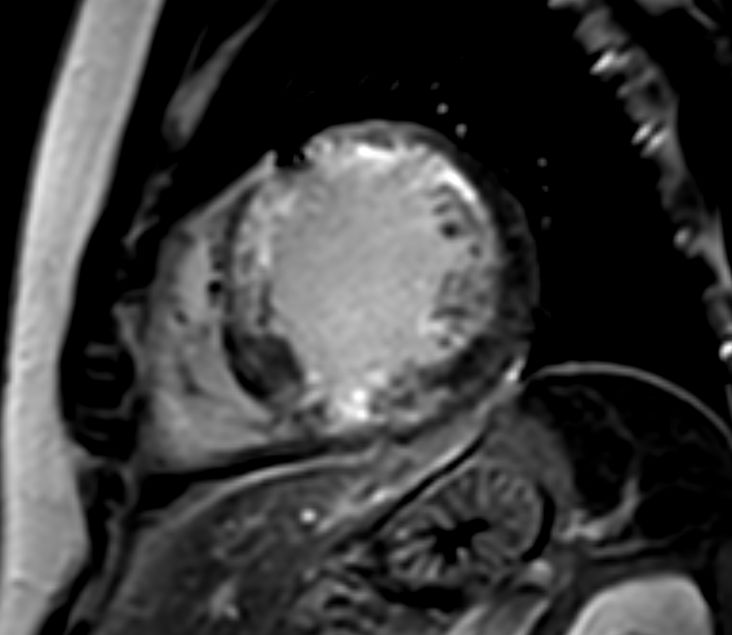

Short axis view 3D PSIR

Short axis view cine